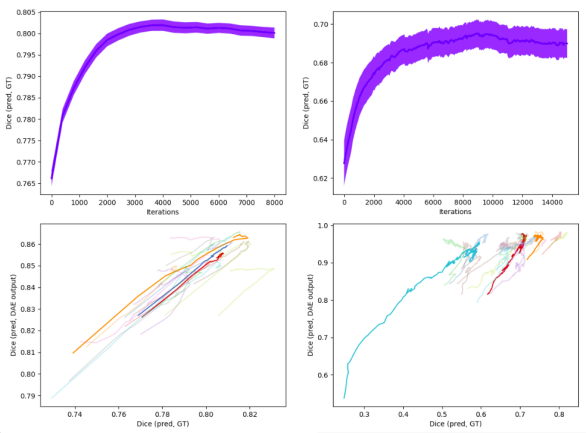

4.4.6 Convergence of Test-Time Adaptation

We note that the convergence of the test-time adaptation is not theoretically guaranteed. However, in our experiments, we find that the adaptation converges across the more than 100 test volumetric images across different anatomies and TDs, and across multiple runs of the experiments. Fig. 5 shows the convergence behaviour of the test-time adaptation. The top row in the figure demonstrates that the adaptation convergences reliably for different TDs. The bottom row shows the correlation between (a) the Dice between the predicted and ground truth segmentation and (b) the Dice between the DAE input and DAE outputs. It can been seen that these two Dice scores are correlated, thus justifying the choice of using the latter for determining the optimal I2NI parameters.